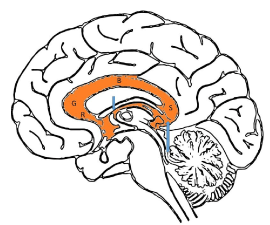

The corpus callosum comprises of 4 main segments; the rostrum, genu, body and splenium (Figure 10).  By 20 weeks, all the components of the corpus callosum are expected to be present at the midline. From then on, the corpus callosum will continue to grow in length and thickness. It will reach an adult appearance by approximately 9 to 10 months of age [44]. One should also be aware that growth of the corpus callosum is typically slower in premature infants compared to infants of the same gestational age [45].

Figure 10. Four main segments of the corpus callosum; the rostrum (R), genu (G), body (B) and splenium (S). Two smaller interhemispheric commissural white matter tracts are the anterior commissure (short blue arrow) and hippocampal commissure (long blue arrow).